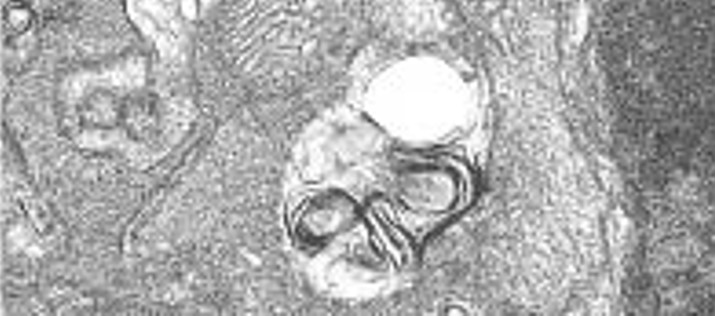

Una investigación pionera contribuirá a mejorar el conocimiento de las enfermedades minoritarias mitocondriales